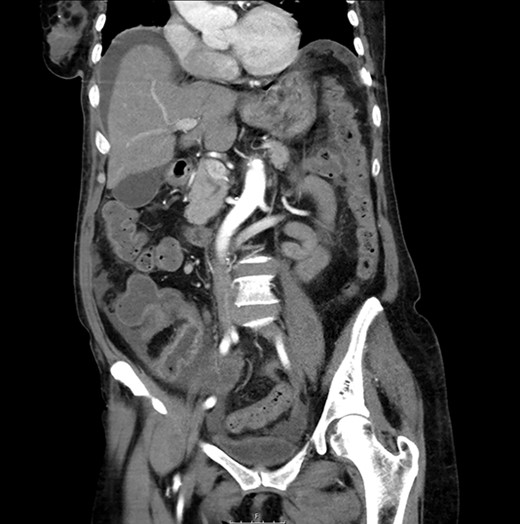

CT scan: sudden change of caliber at the terminal ileum together with signs of intestinal suffering.